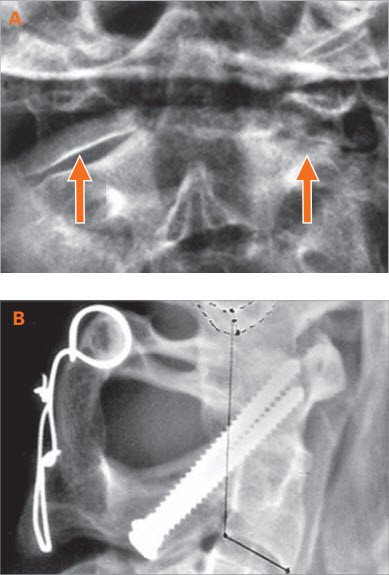

A: Gelenk normal, rechts arthrotisch verändert

B: Die Verschraubung führt zu Schmerzlinderung

Bei schmerzhaften Veränderungen der Gelenke oder Einengung des Nervenkanals kann ein hinterer Zugang gewählt werden. Dabei wird die Nackenmuskulatur nach entsprechendem längs verlaufenden Hautschnitt in der Mitte durchtrennt und von der Wirbelsäule abgelöst. Die schmerzhafte Stelle wird dann mit einem Titanimplantat sorgfältig versteift.